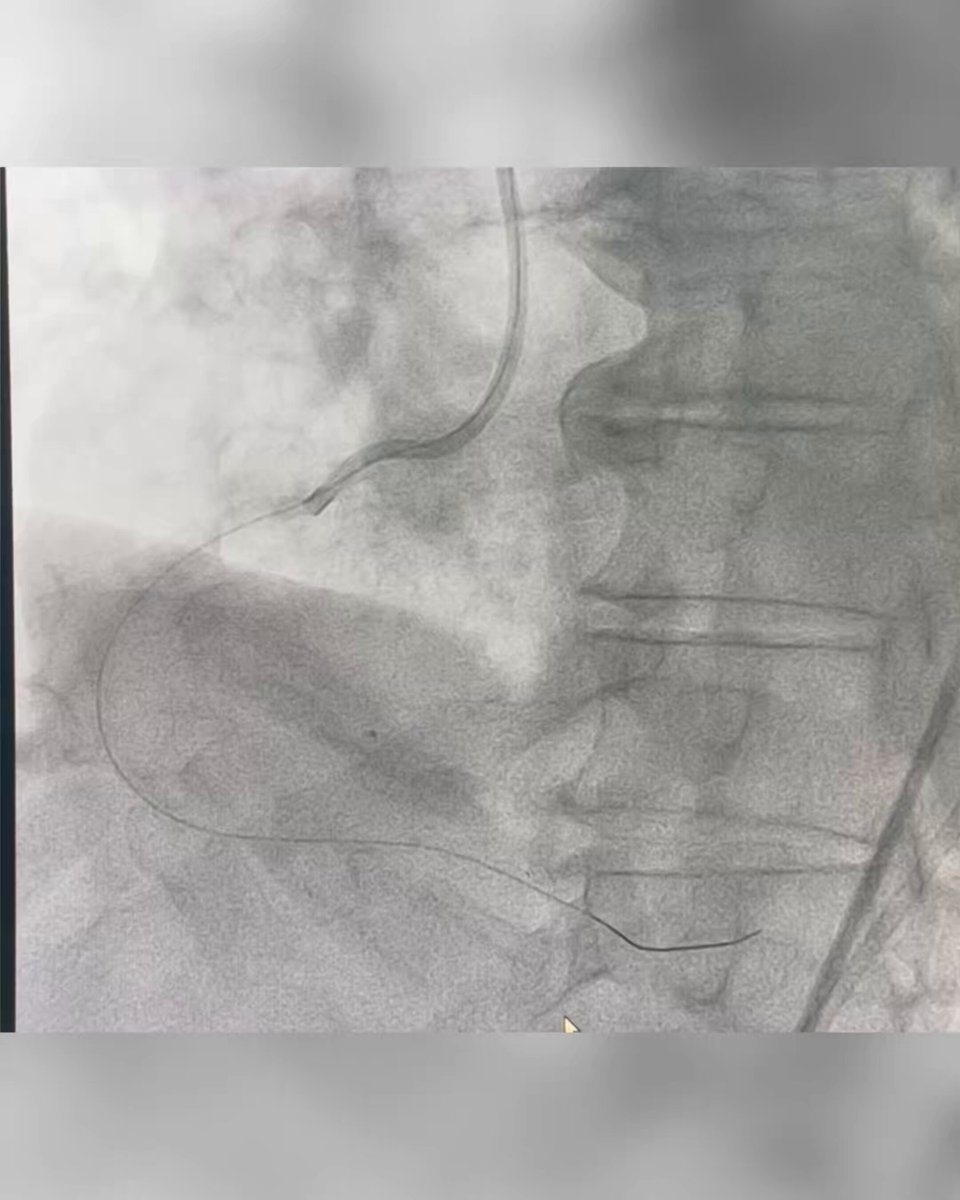

Calcified lesion with coronary laceration, Ping-Pong bailout Watch on X

Calcified PCI Coronary laceration Ping-Pong

Calcified lesion with intra-procedural coronary laceration

Extensive calcified disease complicated by coronary laceration during the procedure. Bailout managed with Ping-Pong dual-guide technique to maintain wire position for both balloon tamponade and covered stent delivery, with definitive sealing using a Papyrus covered stent. Worth reviewing for any operator dealing with complex calcium and perforation preparedness.

Substrate: Severe Ca²⁺

Complication: Laceration

Bailout: Ping-Pong

Sealing: Papyrus